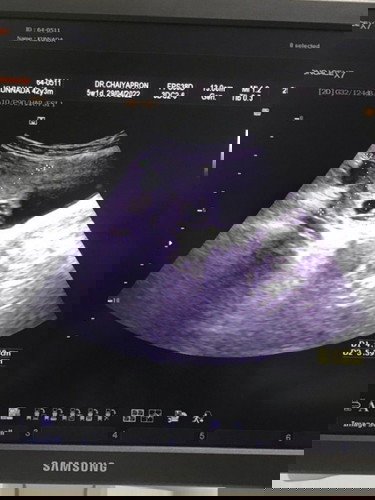

ถุงน้ำรังไข่ระหว่างตั้งครรภ์ 5 สัปดาห์

อัลตราซาวพบถุงน้ำที่รัวไข่ประมาณ 5 เซ็นต์ อันตรายไหมคะ